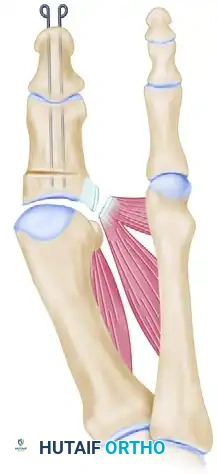

5. Fixation Techniques

Rigid fixation is required to maintain the correction and promote primary bone healing. Several techniques are viable, depending on surgeon preference and bone quality.

Kirschner Wire (K-wire) Fixation

- Primary Wire: Drill a 0.062-inch smooth K-wire through the distal and proximal phalanges while holding the IP joint in a neutral position. Inserting this wire 2 to 3 mm plantar to the tip of the nail facilitates its passage into the medullary canals of both phalanges. Advance the wire across the osteotomy site and into the subchondral bone of the proximal phalanx base.

- Rotational Control: Place a second 0.062-inch or 0.045-inch K-wire parallel to the first to control rotation at the osteotomy site.

- Capsular Protection: If the medial capsule is too attenuated to hold the hallux reduced on the metatarsal head, the K-wires can be driven across the MTP joint and into the metatarsal head to temporarily protect the capsular repair.

- Crossed Wires: If parallel wires are insufficient to maintain the corrected position, two crossed K-wires can be placed from distal to proximal. The ends are bent outside the skin to prevent migration.